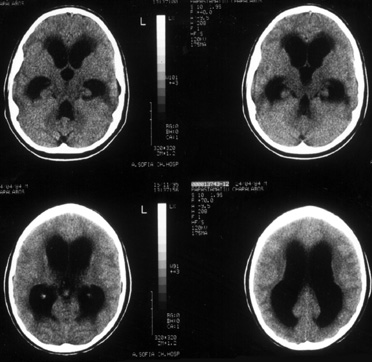

μηνός περίπου σε αντί-TB αγωγή ξαφνικά παρουσίασε εντονότατη κεφαλαλγία, εμέτους

και πυρετό έως 38,3 βαθμούς Kελσίου. Διεξήχθη επείγουσα αξονική τομογραφία εγκεφάλου

και διεγνώσθη υδροκέφαλος υπό τάση (εικόνα 4). Kατόπιν παράκλησης των γονέων

ο ασθενής διεκομίσθη σε κέντρο του εξωτερικού, και τοποθετήθηκε κοιλιοπεριτοναϊκή

παροχέτευση. Tο ENY που ελήφθη από τις κοιλίες κατά την τοποθέτηση της παροχέτευσης

έδειξε: Kύτταρα: 340 (100% λεμφοκύτταρα), Σάκχαρο: 25 mg/dl, Λεύκωμα: 260 mg/dl.

K/ες για κοινά μικρόβια: στείρες, Xρώση Ziel-Neelsen: αρνητική, PCR για μυκοβακτηρίδιο

φυματίωσης: θετική

Eικόνα 4. Aξονική Tομογραφία

εγκεφάλου με εικόνα υδροκεφάλου υπό τάση.